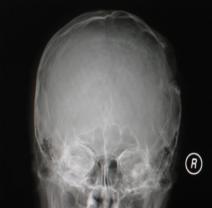

头颅正侧位片:可见右顶部颅骨缺损区,局部软组织隆起,类长圆形,缺损边缘不规则、骨质密度增高合并骨质破坏密度减低,隆起如火山口状(图1)。

图1:(1)正位相见右顶部骨质缺损,局部软组织隆起,边缘不规则,骨质密度增高合并骨质破坏密度减低,隆起如火山口状;(2)侧位相见颅骨缺损区,类似长圆形,缺损边缘不规则